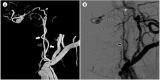

Dural arteriovenous fistula (D-AVF) at the foramen magnum is an extremely rare disease entity. It produces venous hypertension, and can lead to progressive cervical myelopathy thereafter. On the other hand, the venous hypertension may lead to formation of a venous varix, and it can rarely result in an abrupt onset of subarachnoid hemorrhage (SAH) when the venous varix is ruptured. The diagnosis of D-AVF at the foramen magnum as a cause of SAH may be difficult due to its low incidence. Furthermore, when the D-AVF is fed solely by the ascending pharyngeal artery (APA), it may be missed if the external carotid angiography is not performed. The outcome could be fatal if the fistula is unrecognized. Herein, we report on a rare case of SAH caused by ruptured venous varix due to D-AVF at the foramen magnum fed solely by the APA. A review of relevant literatures is provided, and the treatment modalities and outcomes are also discussed.